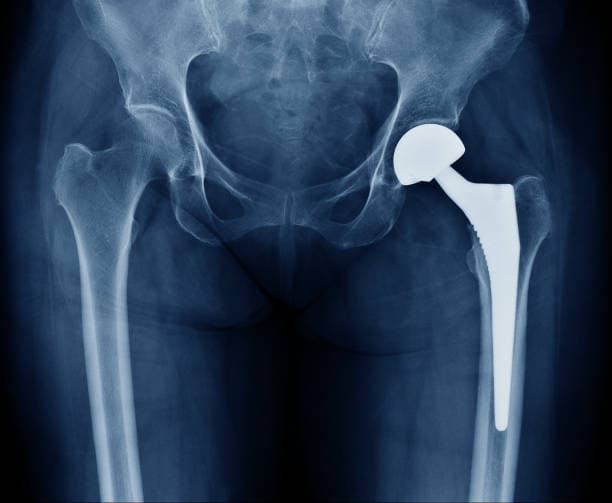

Total hip arthroplasty (THA) is the most common and widely performed hip replacement procedure. It involves replacing both the acetabulum (hip socket) and the femoral head (the ball) with prosthetic components made of metal, ceramic, or plastic. This procedure is typically recommended for patients with severe osteoarthritis, rheumatoid arthritis, or significant hip fractures that impair mobility and cause chronic pain. THA aims to relieve pain, improve joint function, and enhance the patient's quality of life. The prosthetic components are designed to mimic the natural movement of the hip joint, allowing for smooth and pain-free motion.

There are different types of hip arthroplasty, including total hip replacement, where both the femoral head and the acetabulum are replaced, and partial hip replacement, which involves only the femoral head. The choice of procedure depends on factors such as the patient's age, activity level, and the extent of joint damage. Minimally invasive techniques are also available, which involve smaller incisions and aim to reduce recovery time and postoperative discomfort.